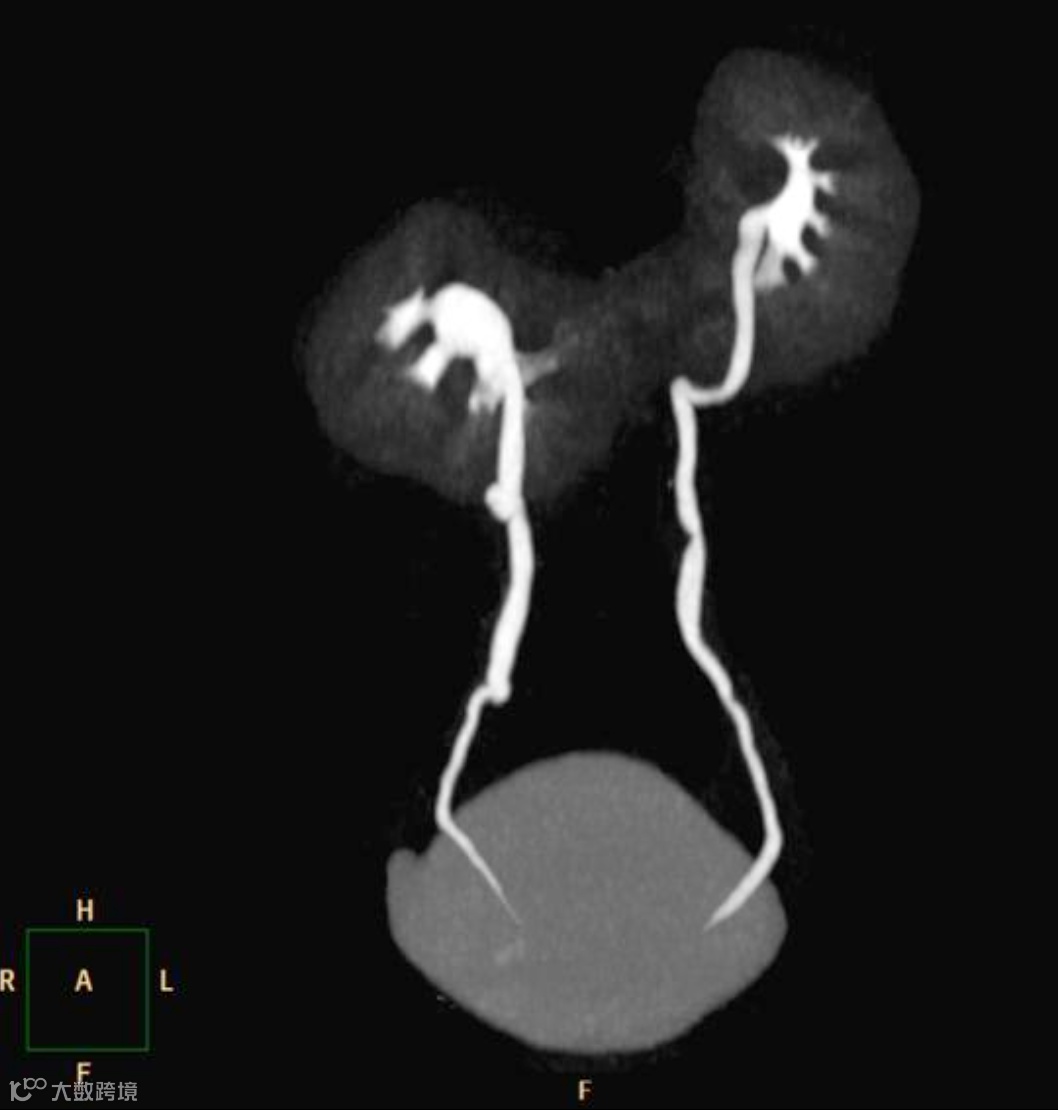

CTU能更清晰地显示旋转异常的肾盂肾盏和输尿管起始部。

女,25岁,马蹄肾。肾脏下极相连,呈马蹄形,肾皮质厚度正常,泌尿系统未见梗阻扩张。